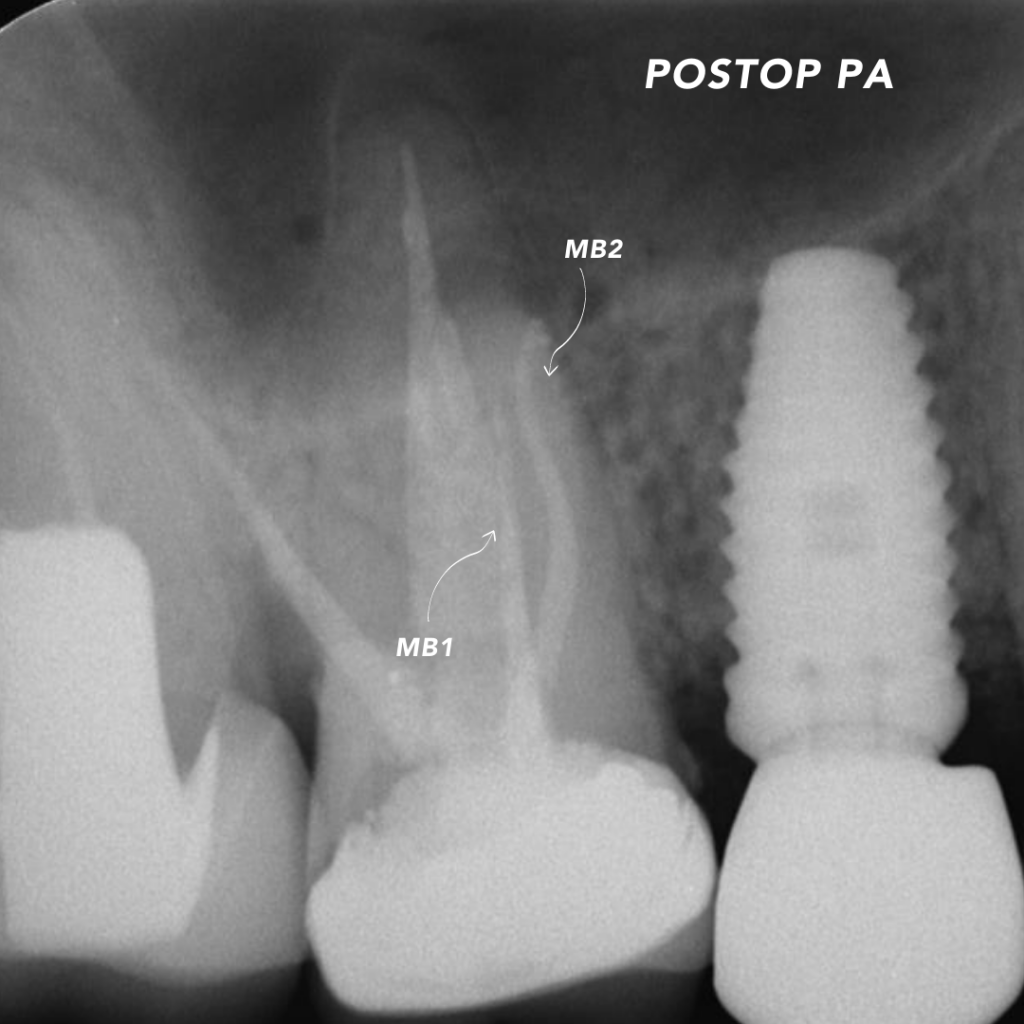

After that, the recall appointments started coming in, and the radiological healing was quick and comparable to those I had treated in multiple visits in the past. Over the last 18 months of practice, I’ve utilized the Waterlase on every single case that comes into my office. It’s so versatile that I can also use it for access preparation, cleaning sinus tracts, gingival augmentation, and crown lengthening.

Waterlase has helped me provide superior care to patients and become more efficient with my time. I have been able to offer full-service endodontic treatment and restorative care that translates into time and cost-effectiveness for the patient. It has taken us forward with the most cutting-edge technology available to deliver world-class endodontics in Sydney’s Hills District. With Watelase at my side, I now feel more secure while tackling technically difficult cases.